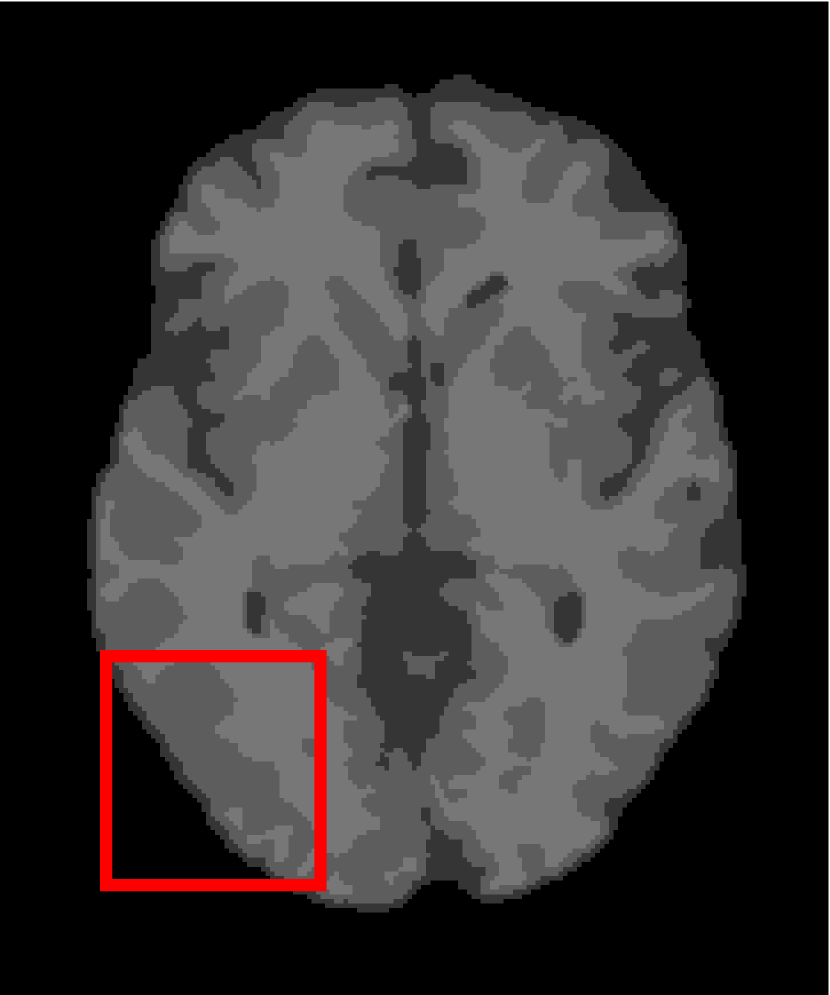

4.4.2 Results on Medical Images

Next, we representatively segment five medical images from BrianWeb. They are represented as five slices in the axial plane with a sequence of 70, 80, 90, 100 and 110, which are generated by T1 modality with slice thickness of 1mm resolution, 9% noise and 20% intensity non-uniformity. Here, we set c=4𝑐4c=4 for all cases. The comparison between WRFCM and its peers are shown in Fig. 9 and Table II. The best values are in bold.

Figure 9: Segmentation results on five medical images. The parameter: ϕ=5.35italic-ϕ5.35\phi=5.35. From top to bottom: noisy images, ground truth, and results of FCM_S1, FCM_S2, FLICM, KWFLICM, FRFCM, WFCM, DSFCM_N, and WRFCM.

By a view of the marked red square in Fig. 9, we find that FCM_S1, FCM_S2, FLICM, KWFLICM and DSFCM_N are vulnerable to noise and intensity non-uniformity. They give rise to the change of topological shapes to some extent. Unlike them, FRFCM and WFCM achieve sufficient noise removal. However, they produce overly smooth contours. Compared with its seven peers, WRFCM can not only suppress noise adequately but also acquire accurate contours. Moreover, it yields the visual result closer to ground truth than its peers. As Table II shows, WRFCM obtains optimal SA, SDS and MCC results for all five medical images. As a conclusion, it outperforms its peers visually and quantitatively.